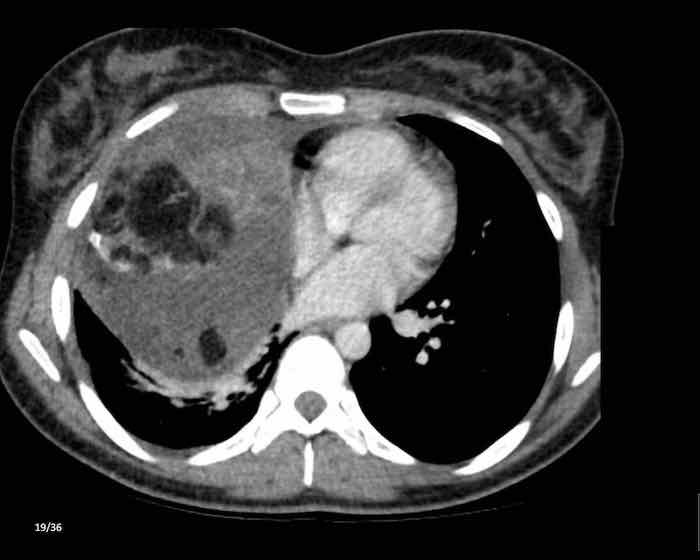

Các hình ảnh này của một nam giới 71 tuổi.

Trên CT ngực, tình cờ phát hiện một khối ở tuyến ức.

Hãy phân tích các hình ảnh. Nhận định của bạn là gì?

Hình ảnh

Một phần tổn thương có ngấm thuốc cản quang và có một số vôi hóa, có thể nằm ở thành nang.

Khi một tổn thương tuyến ức có thành phần đặc, nguyên tắc là… “khi còn nghi ngờ, hãy phẫu thuật cắt bỏ”.

Tổn thương đã được phẫu thuật cắt bỏ dựa trên kết quả CT và kết quả giải phẫu bệnh cho thấy đây là u tuyến ức dạng nang.